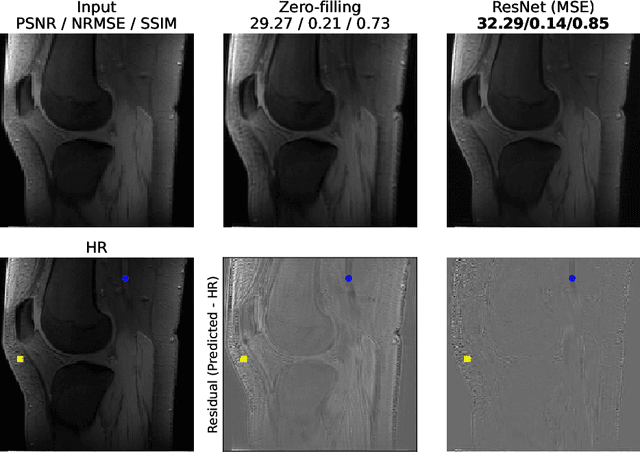

Abstract:The onset of rheumatic diseases such as rheumatoid arthritis is typically subclinical, which results in challenging early detection of the disease. However, characteristic changes in the anatomy can be detected using imaging techniques such as MRI or CT. Modern imaging techniques such as chemical exchange saturation transfer (CEST) MRI drive the hope to improve early detection even further through the imaging of metabolites in the body. To image small structures in the joints of patients, typically one of the first regions where changes due to the disease occur, a high resolution for the CEST MR imaging is necessary. Currently, however, CEST MR suffers from an inherently low resolution due to the underlying physical constraints of the acquisition. In this work we compared established up-sampling techniques to neural network-based super-resolution approaches. We could show, that neural networks are able to learn the mapping from low-resolution to high-resolution unsaturated CEST images considerably better than present methods. On the test set a PSNR of 32.29dB (+10%), a NRMSE of 0.14 (+28%), and a SSIM of 0.85 (+15%) could be achieved using a ResNet neural network, improving the baseline considerably. This work paves the way for the prospective investigation of neural networks for super-resolution CEST MRI and, followingly, might lead to a earlier detection of the onset of rheumatic diseases.